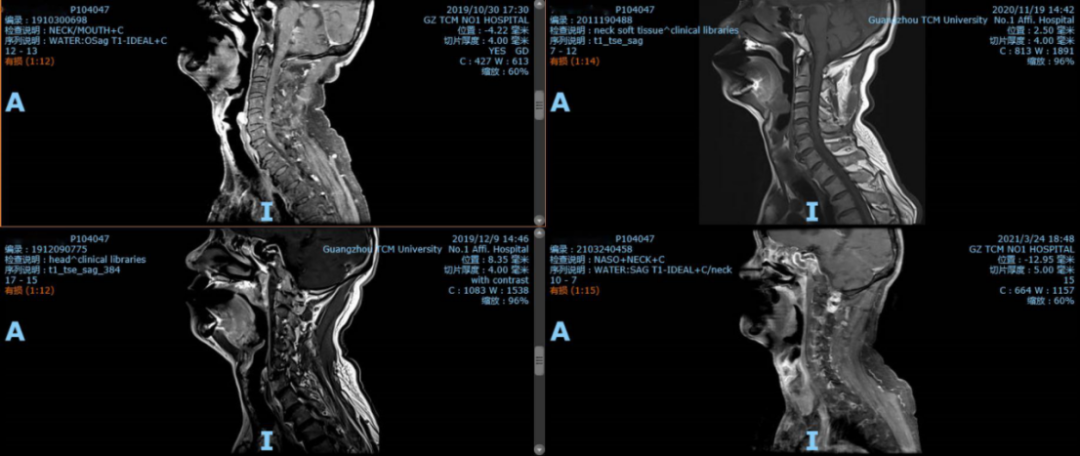

患者化疗联合免疫治疗后,仅PICC置管处皮肤稍发红疼痛,未出现严重副反应,继续守前方进行治疗。患者因化疗副作用,自2019年至今维持中药结合免疫治疗,治疗过程中规律的复查提示舌根部病灶逐渐地缩小。在2021年3月24日复查MR提示舌根部不规则软组织肿块较前明显缩小,达到最佳疗效评价为PR(保持着部分缓解状态)。目前患者以中药及免疫治疗,无任何不适。KPS评分为100分,在控制病灶的同时,带瘤生存,享有较高的生活质量。

注:经过治疗后,病灶逐渐缩小,达到最佳疗效:PR(部分缓解)。